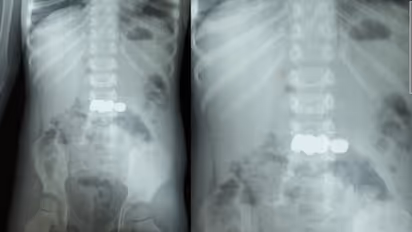

Meppadi: A two-year-old boy was given a new lease on life through an emergency endoscopy at Dr. Moopen's Medical College after accidentally swallowing five batteries while playing. The son of a couple from Bathery Moolankavu swallowed the batteries from a toy. A major disaster was averted thanks to the timely intervention of the doctors.

After noticing the child putting batteries in his mouth, the family immediately rushed him to the medical college. The procedure to remove the batteries was initiated under the leadership of Dr. Suryanarayanan, a specialist in the Gastroenterology department. All five batteries were safely removed through endoscopy. Dr. Akhil and Dr. Anjana also participated in this mission.

Doctors warn that swallowing batteries is life-threatening: There is a possibility of the batteries bursting due to the acidic action in the stomach. If the battery bursts, the released chemicals can cause serious damage to major organs like the intestines and liver. If they could not be removed in time through endoscopy, it would have required complex surgery.